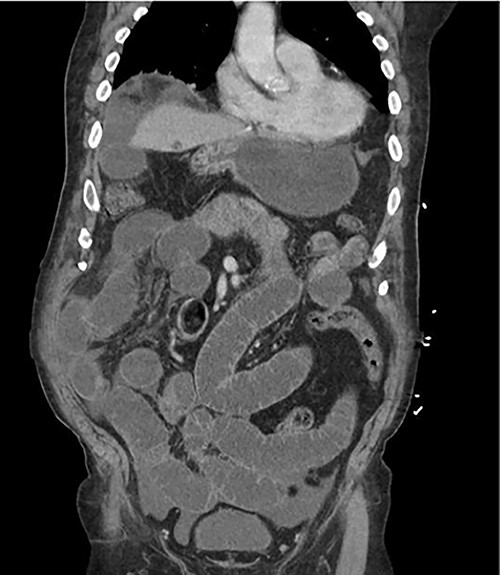

An 81-year-old male with past medical history of coronary artery disease, peripheral arterial disease, hypertension, dyslipidemia, hypothyroidism, benign prostatic hyperplasia, osteoarthritis, sleep apnea, gout and 10-pack year smoking history presented with complaints of abdominal distention and bloating. Patient had been suffering from recurrent bouts of constipation for ~2 weeks with last bowel movement noted to be over 2 days prior to presentation. Patient also complained of numerous episodes of nonbilious non-bloody vomiting. Abdominal computed tomography (CT) scan (Fig. 1) presented findings of a small bowel obstruction with transition point at the level of the terminal ileum. Notably, patient was also positive for coronavirus disease 2019 (COVID-19) infection. General surgery was consulted, and patient was initially treated with non-operative management with nasogastric tube and serial abdominal exams. However, a repeat abdominal CT scan (Fig. 2) after 6 days of attempted conservative management showed persistent diffuse small bowel distention and increased ascites. This combined with the fact that the patient had no prior colonoscopies or abdominal surgeries prompted surgical exploration. Patient underwent exploratory laparotomy; intraoperatively, he was found to have a palpable mass at the terminal ileum. A right hemicolectomy with a side-to-side functional end-to-end ileocolonic primary anastomosis was performed. Final pathology revealed diffuse peritoneal malignant mesothelioma with no nodal involvement and negative margins.